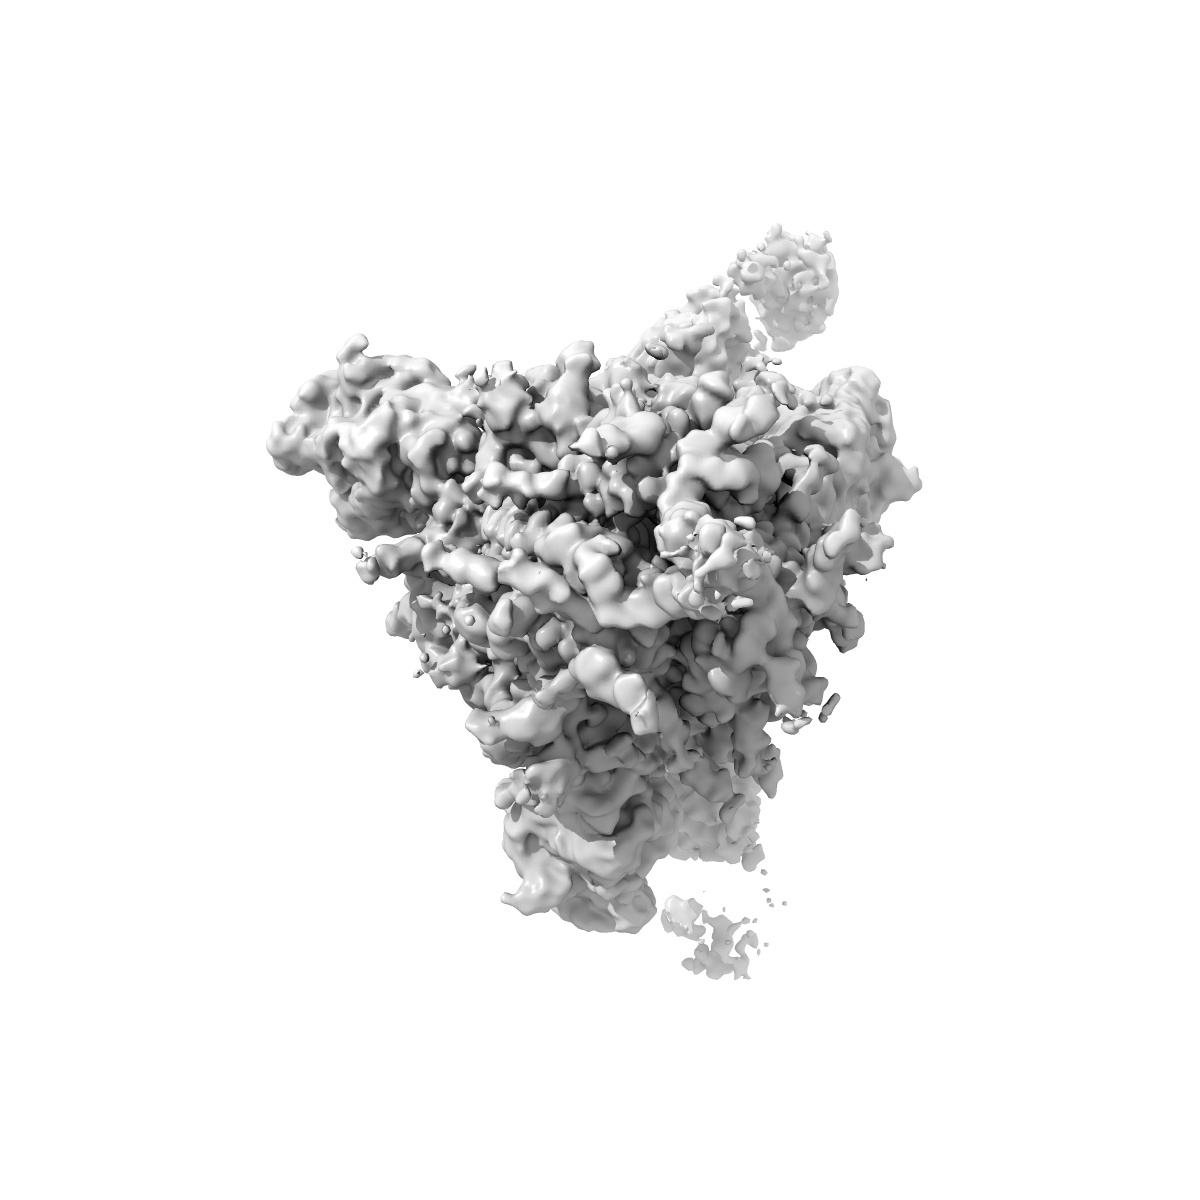

SARS-CoV-2 spike + IMCAS-123

Sample: Cryo-EM structure of SARS-CoV-2 spike + IMCAS-123

Deciphering a reliable synergistic bispecific strategy of rescuing antibodies for SARS-CoV-2 escape variants, including BA.2.86, EG.5.1, and JN.1.

Tong Z, Tong J, Lei W, Xie Y, Cui Y, Jia G, Li S, Zhang Z, Cheng Z , Xing X, Ma H , Deng L, Zhang R, Zhao X, Liu K, Wang Q, Qi J, Huang H, Song R, Su Z, Wu G, Lou J, Gao GF

(2024) Cell Rep , 43 , 114338 - 114338